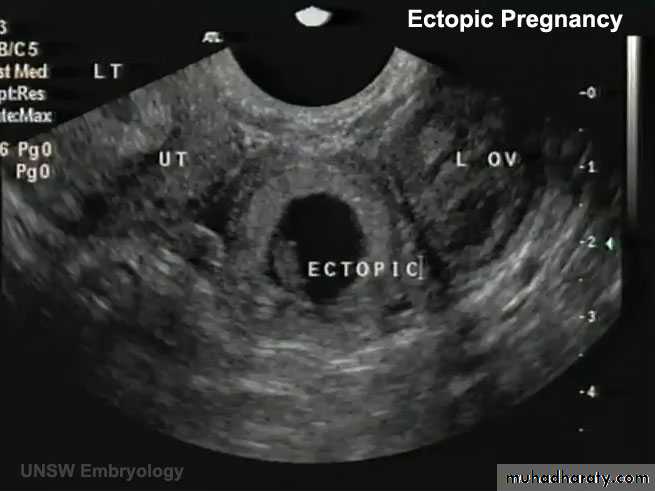

• Transvaginal ultrasound scan (TVS): An intrauterine gestational sac should be visualized at about 4.5 weeks of gestation. The corresponding bHCG at that gestation is around 1500 mIU/ mL. By the time a gestational sac with fetal heart pulsation is detected (at around 5 weeks gestation), bHCG level should be around 3000 mIU/mL.

Thus, if there were discrepancy between the bHCG concentrations and that seen on ultrasound scan (e.g. a high bHCG with no intrauterine pregnancy on ultrasound scan), the differential diagnosis of an ectopic pregnancymust be made.

Identification of an intrauterine pregnancy (gestation sac, yolk sac along with fetal pole) on TVS effectively excludes the possibilityof an ectopic pregnancy in most patients except in those patients with rare heterotopic pregnancy.

The presence of free fluid during TVS is suggestive of a ruptured ectopic pregnancy.